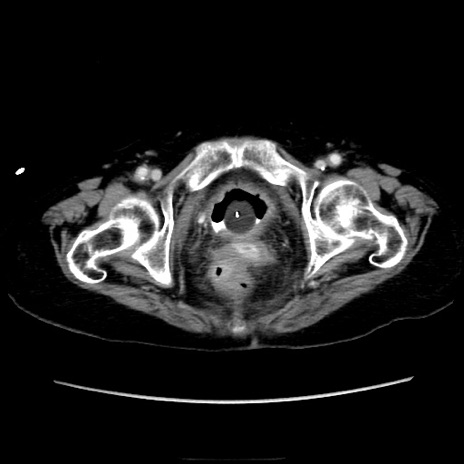

症例40(横断像)

【症例】90歳代女性

【主訴】腹痛・嘔吐

【現病歴】 食欲低下、嘔吐があり昨日他院受診。肺炎と診断され入院となる。入院後より腹部全体に圧痛あり。胃管留置され経過みていたが、症状持続するため、

当院転院となる。

【既往歴】胸椎圧迫骨折、胆石症

【身体所見】腹部:中央に激痛あり、圧痛あり、反跳痛不明

【データ】WBC 17100、CRP 18.82

横断像